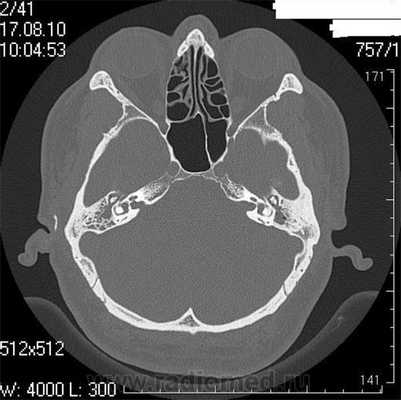

Снимок (томограмма) височных костей в осевой проекции

С помощью КТ височных костей можно выявить любые заболевания воспалительного, травматического, опухолевого характера. Метод применяется для диагностики следующих патологий:

объемных образований, кист костной ткани и слухового аппарата;

воспалительных процессов (мастоидиты, отиты, остеомиелиты);

травматических повреждений (трещины, переломы);

дегенеративных изменений (отосклероз, дисплазия);

Большим преимуществом КТ перед другими диагностическими методами является возможность получения трехмерной модели височной кости. 3D-изображение необходимо перед хирургическим вмешательством, часто по поводу установки имплантата внутреннего уха, поскольку дает максимально четкое представление об особенностях анатомии у конкретного пациента.

Компьютерная томография является оптимальным вариантом для исследования костей, в том числе черепа. Костная ткань хорошо поглощает рентгеновские лучи, в результате получают четкие ее изображения. Данный метод незаменим в диагностике скрытых переломов и трещин, он хорошо выявляет деструктивные изменения.

На КТ-снимке виден перелом пирамиды височной кости (указан стрелками)